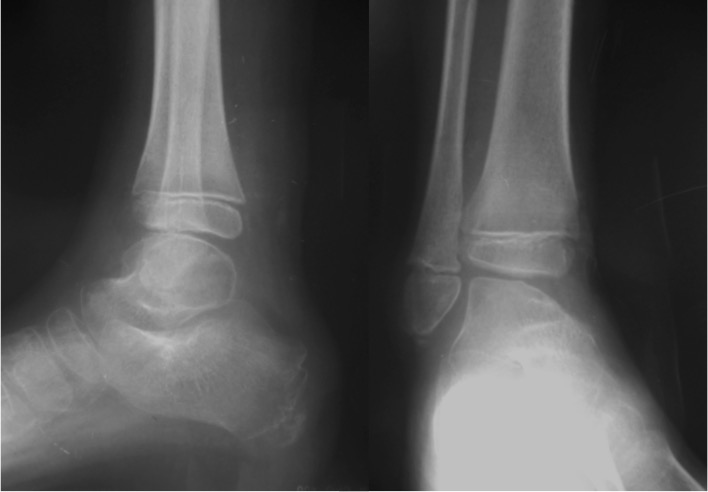

Fracturas fisarias Salter-Harris VI de tobillo y pie. [Salter-Harris VI fractures of the foot and ankle.]